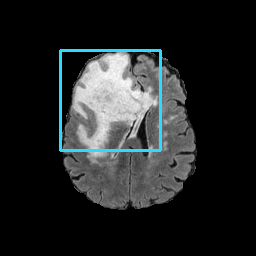

Refer to caption

(a) CT images.

(b) MRI images.

Figure 6: Lossy compression based attack on CT images (a) and MRI images (b) with a specific channel numbers (C8050\mathrm{C^{50}_{80}}) for the EP and IT Scenarios. StolenEPD1\mathrm{Stolen}^{\mathrm{D1}}_{\mathrm{EP}} denotes the decompressed images in the EP Scenario with a reduced D1 decoder.

Compression-Fidelity Compromise. Based on the previous results, we have selected the decoder D1D1 and the configuration of the latent and hyperlatent variables C8050\mathrm{C^{50}_{80}}, as the optimal architecture of the HiFiC encoder-decoder pair. In Fig. 6, we display more specifically the compression and reconstruction quality performances. In terms of reconstruction quality, we obtain a PSNR of approximately 40 for CT images and around 38 for MRI images while the MS_SSIM values are close to 1. This indicates an excellent perceptual quality of the reconstructed images that are hardly discernible from the original ones. In terms of compression efficiency, the Pratio\mathrm{P}_{\mathrm{ratio}} for CT images is approximately 0.015, indicating that the lossy image compression-based attack generated compressed images are 67 times smaller than those produced by the lossless zipped image compression-based attack. For MRI images, the Pratio\mathrm{P}_{\mathrm{ratio}} is around 0.12, 10 times higher than that of CT images, which can be attributed to the presence of a large uniform background in the skull-stripped original MR images.

A visual comparison between target and stolen images is available in Fig. 7. We observe that the stolen images from IT Scenario closely resemble the input ones, particularly in the tumor regions, whereas stolen images from EP Scenario exhibit blurring artifacts in finer details. In both cases, the stolen images reconstructed by D1D1 demonstrate a comparable quality to those reconstructed by DD, thus further confirming the effectiveness of the reduced decoder D1D1.